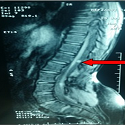

Ostéo arthrite tuberculeuse de la cheville et spondylodiscite: une association rare

Samia Frioui, Sonia Jemni

PAMJ. 2015; 21: 259. Published 07 August 2015